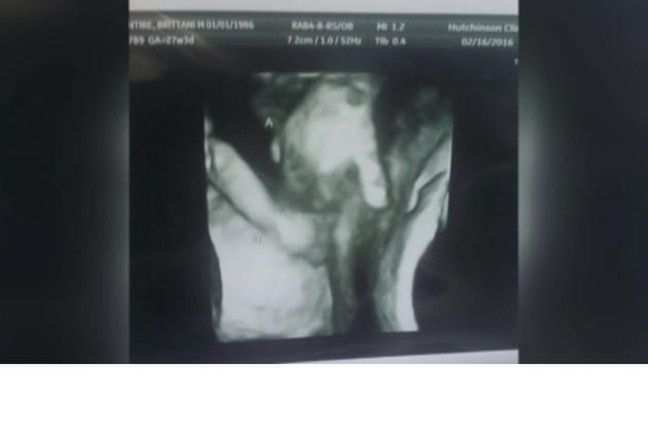

W ostatnich dniach w internecie pojawił się wzruszający obrazek: sonogram ukazujący moment, kiedy umierający brat bliźniak trzyma w łonie matki rękę siostry. Przyszli rodzice, Ian i Brittani McIntire, byli załamani, kiedy dowiedzieli się, że jedno z bliźniąt nie przeżyje.

Lekarze zajmujący się parą z Kansas stwierdzili na podstawie badań prenatalnych, że nienarodzony syn Mason ma wadę serca oraz mózgu. Jednak rodzina wciąż wzrusza się na widok zdjęcia zrobionego za pomocą sonogramu, na którym uchwycono, jak bliźnięta trzymają się za ręce. Na ujęciu widać, jak syn Mason, po lewej, trzyma małą dłonią palec siostry, Madilyn.

Rodzice bliźniąt uważają, że ta wyjątkowa chwila pomiędzy rodzeństwem to nie przypadek. Dzięki temu zdjęciu wiedzą, że będą mieli ich cząstkę razem, na zawsze. Matkę bliźniąt pociesza myśl, że jeśli malec nie przeżyje, nie będzie sam.

Lekarze poinformowali parę, że jedyną szansą na przeżycie syna jest przeprowadzenie operacji serca, jednak nie mogą ryzykować, ponieważ u rozwijającego się dziecka występują również wady mózgu. Lekarze nie są w stanie pomóc Masonowi, dlatego rodzice muszą z niepokojem czekać na rozwój wypadków i na to, czy w końcu będą mieli szansę poznać syna.

Bliźnięta mają urodzić się we wrześniu. Jednak lekarze ostrzegają rodziców, że ich syn, niestety, może umrzeć jeszcze w łonie matki przed spodziewaną datą porodu.